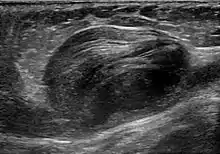

A false aneurysm, or pseudoaneurysm, is a collection of blood leaking completely out of an artery or vein but confined next to the vessel by the surrounding tissue. This blood-filled cavity will eventually either thrombose (clot) enough to seal the leak or rupture out of the surrounding tissue.[3]:357

Pseudoaneurysms can be caused by trauma that punctures the artery, such as knife and bullet wounds,[4] as a result of percutaneous surgical procedures such as coronary angiography or arterial grafting,[5] or use of an artery for injection.[6]